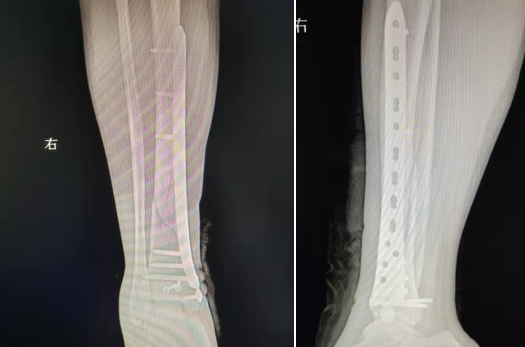

典型病例:女性,56歲,術(shù)前CT提示脛骨中下段骨折,移位明顯。

術(shù)后正側(cè)位片提示骨折達(dá)解剖復(fù)位,力線恢復(fù)正常。